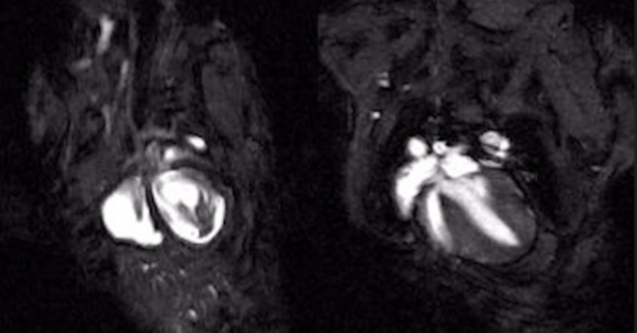

看着健康却突然猝死?这种盯上年轻人的心脏病,科学家终于找到救命方法

Circulation: Heart Failure

图片

@生物世界